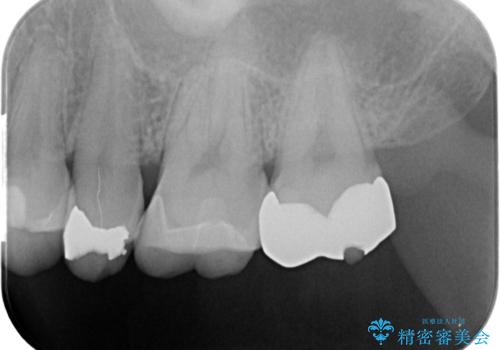

- 銀歯を無くしたいとの事で来院。

拡大鏡下でメタルを除去し虫歯がないことを確認してから白い詰め物、被せ物で治療を行いました。

- ジルコニアクラウンスタンダード・仮歯 12.1万円 e-maxインレー・7.7万円費用は治療当時の料金となります

適合の良い詰め物、被せ物が入りました。